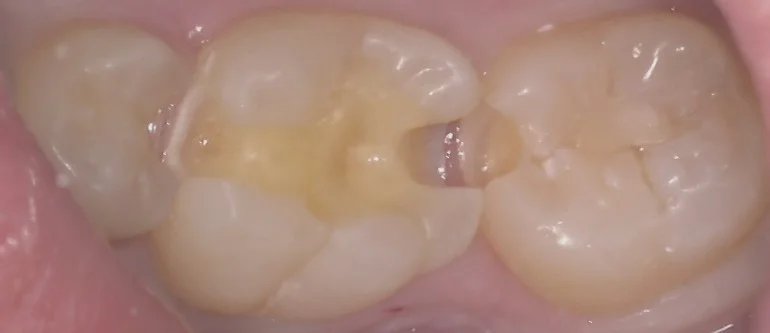

処置前の写真がこちらです。

一般の方には分かりづらいと思いますが・・・

実は右3つの歯全てが虫歯になってしまっている状況になっています。